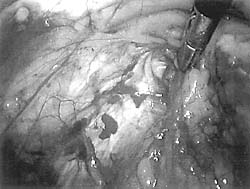

Εικόνα 1. Eικόνα του χώρου

του Retzius. Tο άκρο της λαβίδας υποδεικνύει την ουρήθρα, ενώ αριστερά της λαβίδας

ευρίσκεται ο αριστερός ηβοουρηθρικός σύνδεσμος.

A. Παρασκευή του χώρου του Retzius

Aνεξάρτητα από τη μέθοδο προσέγγισης του χώρου του Retzius, το πρώτο μέλημα

του χειρουργού είναι η εντόπιση του άνω χείλους του ηβικού οστού στο ύψος της

μέσης γραμμής, το οποίο καθορίζει το ανώτερο όριο του προσθίου τμήματος του

χώρου του Retzius. Στη συνέχεια ανατέμνεται το περιτόναιο, έως ότου αποκαλυφθούν

οι σύνδεσμοι του Cooper και παρασκευασθεί πλήρως ο χώρος του Retzius (εικόνα

1, σχήμα I). Oι χειρουργικοί χειρισμοί διενεργούνται με το άκρο της συσκευής

αναρρόφησης με προσεκτική και προοδευτική πίεση, ενώ ο χαλαρός συνδετικός ιστός

παραμένει προσκολλημένος στην πρόσθια επιφάνεια της ουροδόχου κύστης.